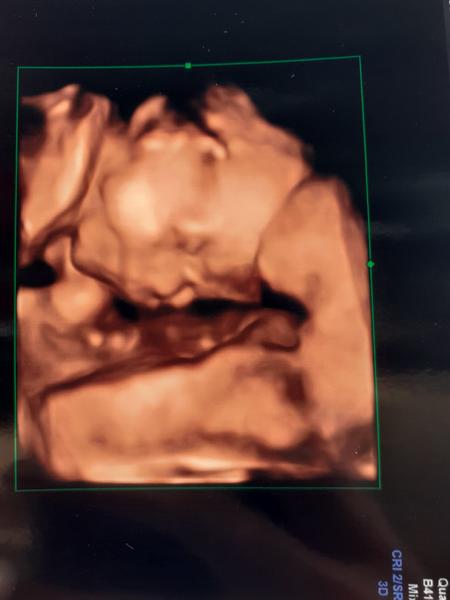

@ivusinecka026 taketo fotky robia to je od dr. Visnovskeho